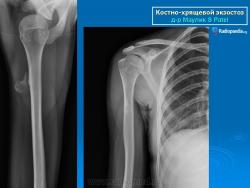

Локализация остеохондромы: частота поражения отдельных костей различна; нижний коней бедренной кости, верхние отделы плечевой и большеберцовой костей поражаются более чем у половины больных. На всем протяжении остеохондрома покрыта надкостницей. Она может быть обнаружена и в других костях, за исключением костей лицевого черепа. Все же поражение костей позвоночника, кистей рук и стоп встречается редко. При рентгенологическом исследовании видна типичная картина узкого или широкого выроста вблизи эпифизарной части пораженной кости. Обычно плотность узла неоднородная, имеются многочисленные плотные участки, соответствующие обызвествленным хрящевым долькам. Хрящевая «шапочка» большей частью не определяется, поскольку хрящ остается необызвествленным. Она может быть выявлена только при магнитно-резонансной томографии.